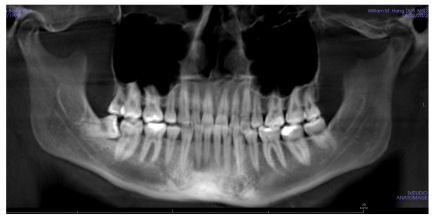

Panoramic. My LR8 (lower right 8/third molar/wisdom tooth) is mesially (towards the center line) inclined and impacted here. We’re attempting to upright it with Invisalign as of April 2026.

• Intermolar Width: 31 mm

• Lower Arch Alignment: Mild Crowding

• Relative AP Molar Relationship: Class II Molars

• Transverse Dental Relationship: Edge to Edge Bite R to L

• Missing Teeth: Missing U&L 4’s

• Other Problems: Still has wisdom teeth, LR8 mesially inclined